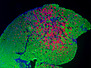

In the intricate microcosm of our bodies, different diseases may interact with each other. For example, researchers are exploring links between serous ovarian cancer (SEOC), the most common form of ovarian tumour, and the herpes simplex virus. Herpes infects over 65% of the world’s population, so is likely to occur in most SEOC patients. It also encodes small molecules, microRNAs, which manipulate gene activity; these are found in the ovaries of SEOC patients at higher levels than in healthy individuals. Each column here shows a section of cancerous tissue, with cell nuclei in blue, the tumour in yellow and surrounding connective tissues in green. In the last two columns, the merged images in the top row reveal the presence of microRNAs (in pink) in the tumour. Specific types of microRNAs are associated with more or less severe cancers, suggesting that further research into their function could help develop potential treatments.